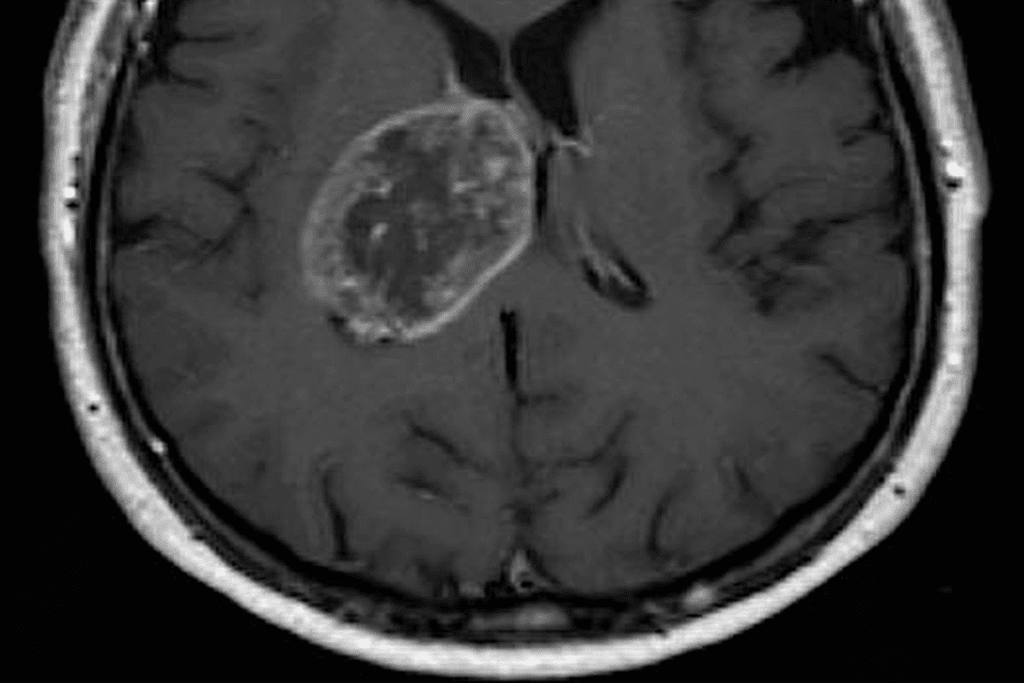

Contrast-Enhanced MRI Techniques

Contrast-enhanced MRI uses a contrast agent to highlight brain areas. It’s great for spotting different tumors and their boundaries.

The contrast agent shows up in areas with blood-brain barrier issues. This makes tumors stand out on MRI images. It boosts diagnostic accuracy and helps plan treatment.

Accuracy of MRI in Brain Tumor Diagnosis

Understanding how well MRI works in finding brain tumors is key. MRI is a top tool for spotting and studying brain tumors. It does this thanks to its clear images.

MRI is great at showing soft tissues, which helps find tumors. How well MRI works depends on the MRI type and the doctor’s skill.

Statistical Success Rates in Tumor Detection

Research shows MRI is very good at finding brain tumors. The success rate of MRI scans changes based on the tumor type and where it is. For example, a study showed MRI found brain tumors 95% of the time and correctly identified them 90% of the time.

| Tumor Type | MRI Sensitivity | MRI Specificity |

| Glioma | 92% | 88% |

| Meningioma | 95% | 92% |

| Metastatic Tumors | 90% | 85% |

The table shows MRI’s success in finding different brain tumors. It shows MRI is a reliable tool for doctors.

Factors Affecting Diagnostic Accuracy

Many things can change how well MRI works for finding brain tumors. The MRI machine’s quality, the use of contrast agents, and the doctor’s experience matter. Also, how the patient moves can affect the image quality.

We need to think about these factors when looking at MRI results. This helps make sure patients get the right treatment. Knowing MRI’s strengths and weaknesses helps doctors make better choices for their patients.